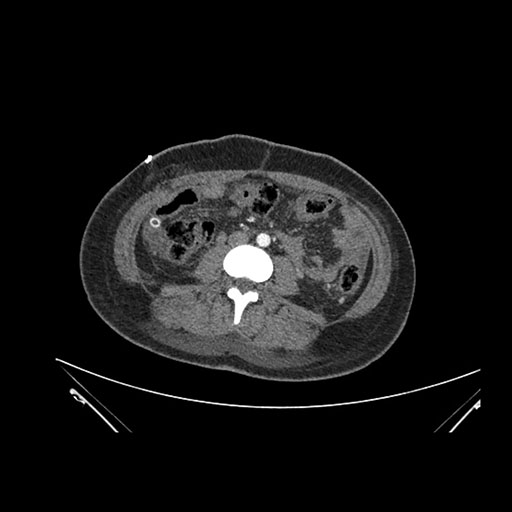

Imaging Analysis

Look through the patient's CT scan to identify any areas of concern for the necessary procedure.

Coronal Venous